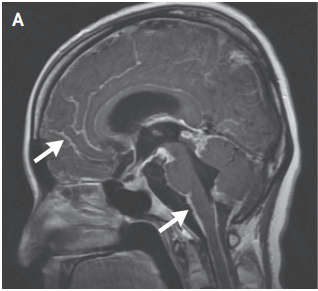

该病例报告[5]报道了一例27岁的女性患者,患者因头痛、呕吐、意识模糊和癫痫发作就诊,在外院神经内科治疗数月未能明确病因。体格检查提示假性脑膜炎,无局灶性神经功能缺损。头部和脊柱MRI T1加权成像显示典型的广泛性脑脊膜线样强化(图A)。

图A.头部MRI影像学表现